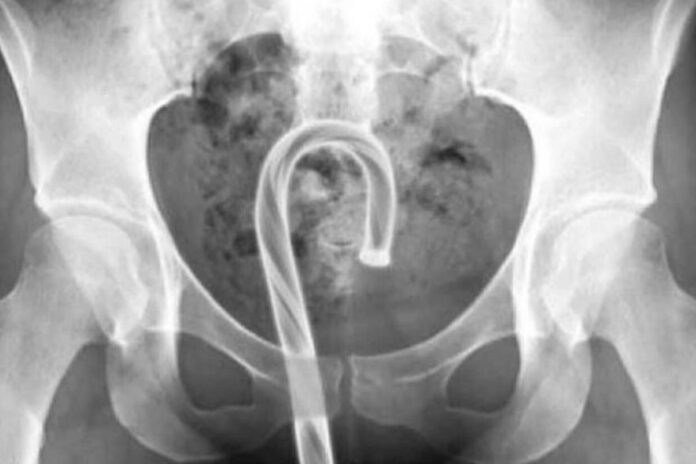

威尔许提到,还有女病患前来就医时,X光扫描发现拐杖糖竟然卡在体内,「任何含糖的东西都应该远离阴道,除了糖果易碎容易折断,糖制品也有可能破坏阴道内微生物环境,导致私密处感染」。